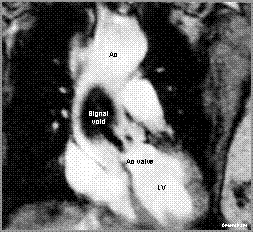

Coronal cine MRI image demonstrates a systolic signal void

originating at the stenotic aortic valve. Ascending aorta is dilated